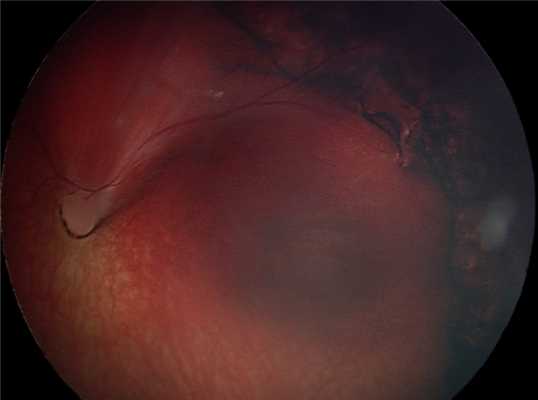

Клинический случай.

Глазное дно ребёнка А. после операции.